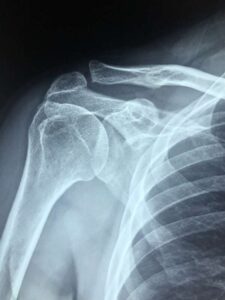

Výpočet bolestného při dopravní nehodě se realizuje obvykle v případech nezaviněné autonehody u zraněného poškozeného. Bolestné je náhrada nemajetkové újmy. Bolestné lze řešit nejen u zlomenin a vážných zranění, ale také u drobných zranění typu pohmožděnin nebo podvrtnutí krční páteře.

Výše bolestného závisí na intenzitě a rozsahu zranění utrpěného autonehodou:

Znalec se při svém výpočtu řídí již zmíněnou Metodikou Nejvyššího soudu. Každé jednotlivé zranění je stanoveno konkrétní položkou a je mu přiřazen určitý počet bodů. Hodnota bodu se určuje podle průměrné hrubé měsíční mzdy za předchozí rok. Za bolest vzniklou v roce 2022 má jeden bod hodnotu 378,39 Kč.

Pro představu – zlomenina žebra se rovná v Metodice 20ti bodům. Pokud tedy poškozený utrpí zlomeninu jednoho žebra (bez dalších komplikací) při autonehodě v březnu 2022, bude mu příslušet 7.568,- Kč za vytrpěnou bolest.